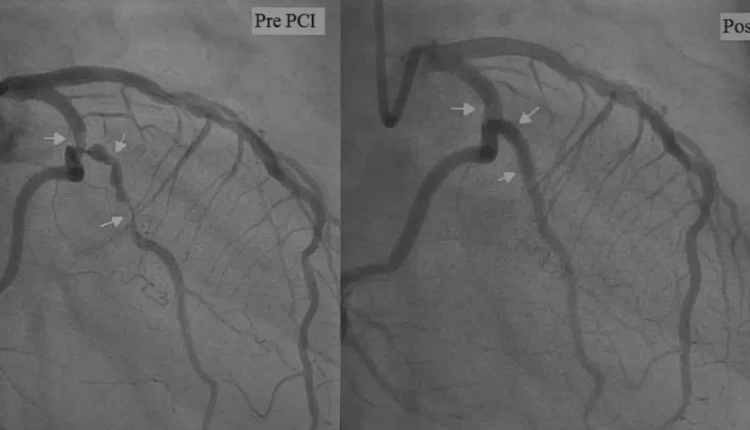

Anjiyo, tıbbi adıyla “koroner anjiyografi”, kalp damarlarının röntgen ışınları ile görüntülenmesini sağlayan bir işlemdir. İnce bir kateter yardımıyla kasık ya da el bileğinden girilerek kalbe ulaşılır ve damarların içerisine kontrast madde (boya) enjekte edilir. Bu boya sayesinde damar yapısı ve olası tıkanıklıklar net şekilde görülebilir.

Anjiyo işlemi genellikle lokal anestezi altında yapılır ve hastanın bilinci açıktır. Ağrısız ve kısa süren bir işlemdir; çoğu zaman 15-30 dakika arasında tamamlanır. Eğer tıkanıklık saptanırsa, aynı seansta müdahale edilerek damar açılabilir.

Eğer anjiyo sırasında damar tıkanıklığı saptanırsa, aynı seansta balonla açma işlemi yapılabilir ve damar içine stent yerleştirilebilir. Ancak bazı durumlarda tıkanıklık çok yaygın veya karmaşıksa, bu hastalara bypass ameliyatı önerilebilir.